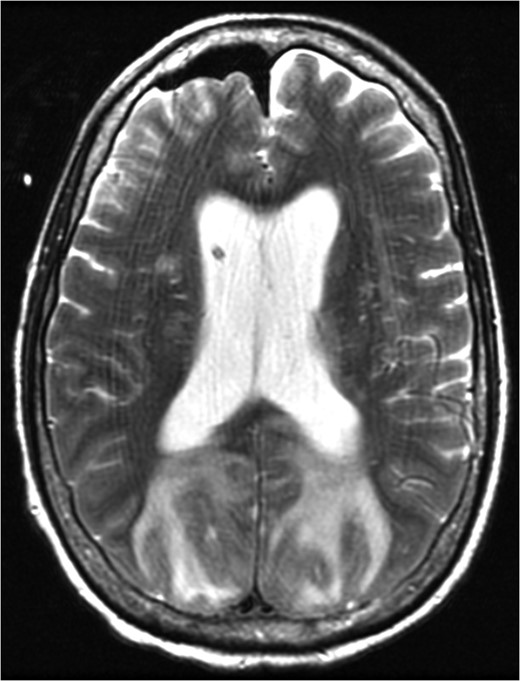

MRI brain 3 months post-diagnosis, Axial T2 sequence. Normalization of imaging with resolution of vasogenic edema and pneumocephalus.